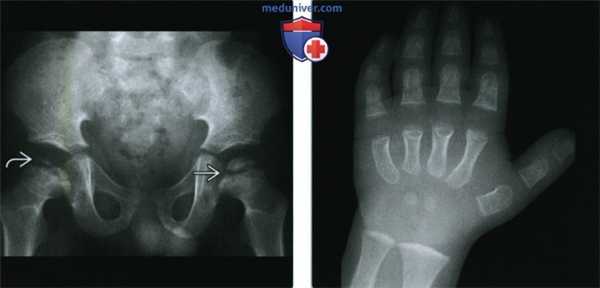

(Справа) Рентгенография кисти в ПЗ проекции, этот же пациент: определяются вспомогательные признаки - несколько пястных костей еще не визуализируются, отсутствуют эпифизы фаланг. Скелетный возраст кисти соответствует у новорожденному, а не четырехлетнему ребенку. Признаки характерны для гипотиреоза.

(Слева) Рентгенография таза в ПЗ проекции у четырехлетнего ребенка: определяется фрагментация эпифиза головки бедренной кости (обозначается термином «кретиноидное бедро»). Отмечается расширение пластинок роста в обоих тазобедренных суставах. Данные указывают на задержку развития скелета.